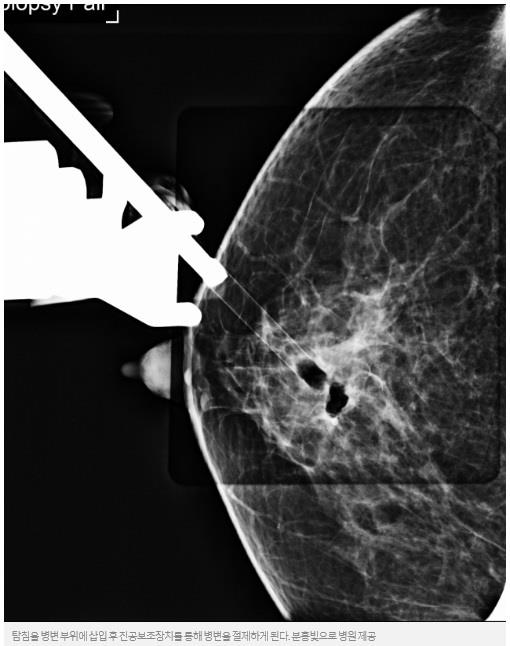

![[건강플러스] 가슴 속 하얀 점…유방 석회화 세심한 검사 필요](http://mastopia.com/pds/editor/imaeil_com_20220118_174020.jpg)

유방엑스선촬영에서 나타나는 석회화는 그 모양을 보면 암인지 여부를 어느 정도 구별할 수 있다. 그러나 모양만으로는 암인지 여부를 구별할 수가 없는 경우에는 조직검사를 실시해야 한다.

과거에는 석회화는 외과적 수술로 조직검사를 해야하다보니 유방에 큰 흉터가 남게 되는 경우가 많았지만, 최근에는 입체정위 진공절제술을 통해 흉터가 거의 없이 석회화를 절제할 수 있게 됐다.

이 병원장은 "입체정위 진공절제술은 컴퓨터 계측장치를 이용해 유방내의 석회화의 위치를 확정하고, 그 위치에 맘모톰이라고 통칭되는 진공보조장치를 삽입해 석회화를 절제하는 방식"이라면서 "최근에 개발된 3차원 입체정위법, 즉 디지털 유방단층합성법은 기존의 2차원 입체정위법에 비해 더 정확하게 석회화 위치를 정할 수 있고, 시술시간이 짧으면서 방사선 피폭량도 적다는 장점이 있다"고 덧붙였다.